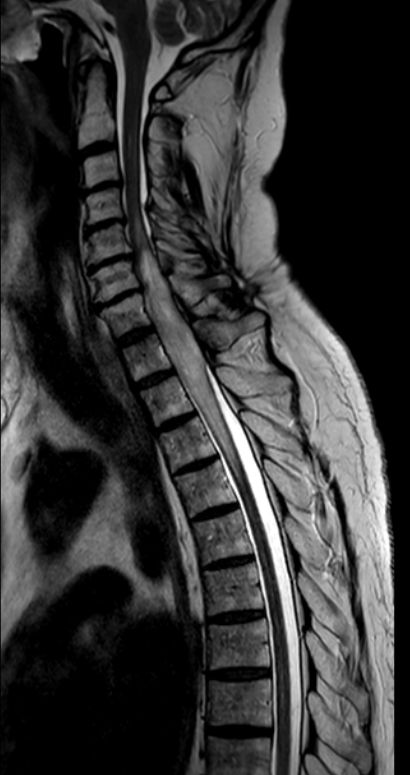

Myelon 63-jähriger Mann mit Querschnittssymptomatik. Auch nach Dekompression keine Motorik oder Sensorik der unteren Körperhälfte.

MRT T2W-Bild. Hier ist die Degeneration des Myelons unterhalb des Tumors erkennbar.